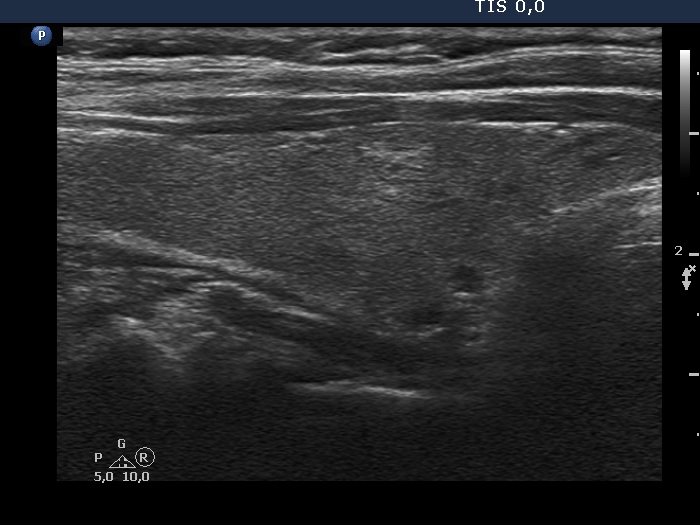

Case cons100_065 (ultrasonographic picture 3)

Right lobe, another longitudinal scan.